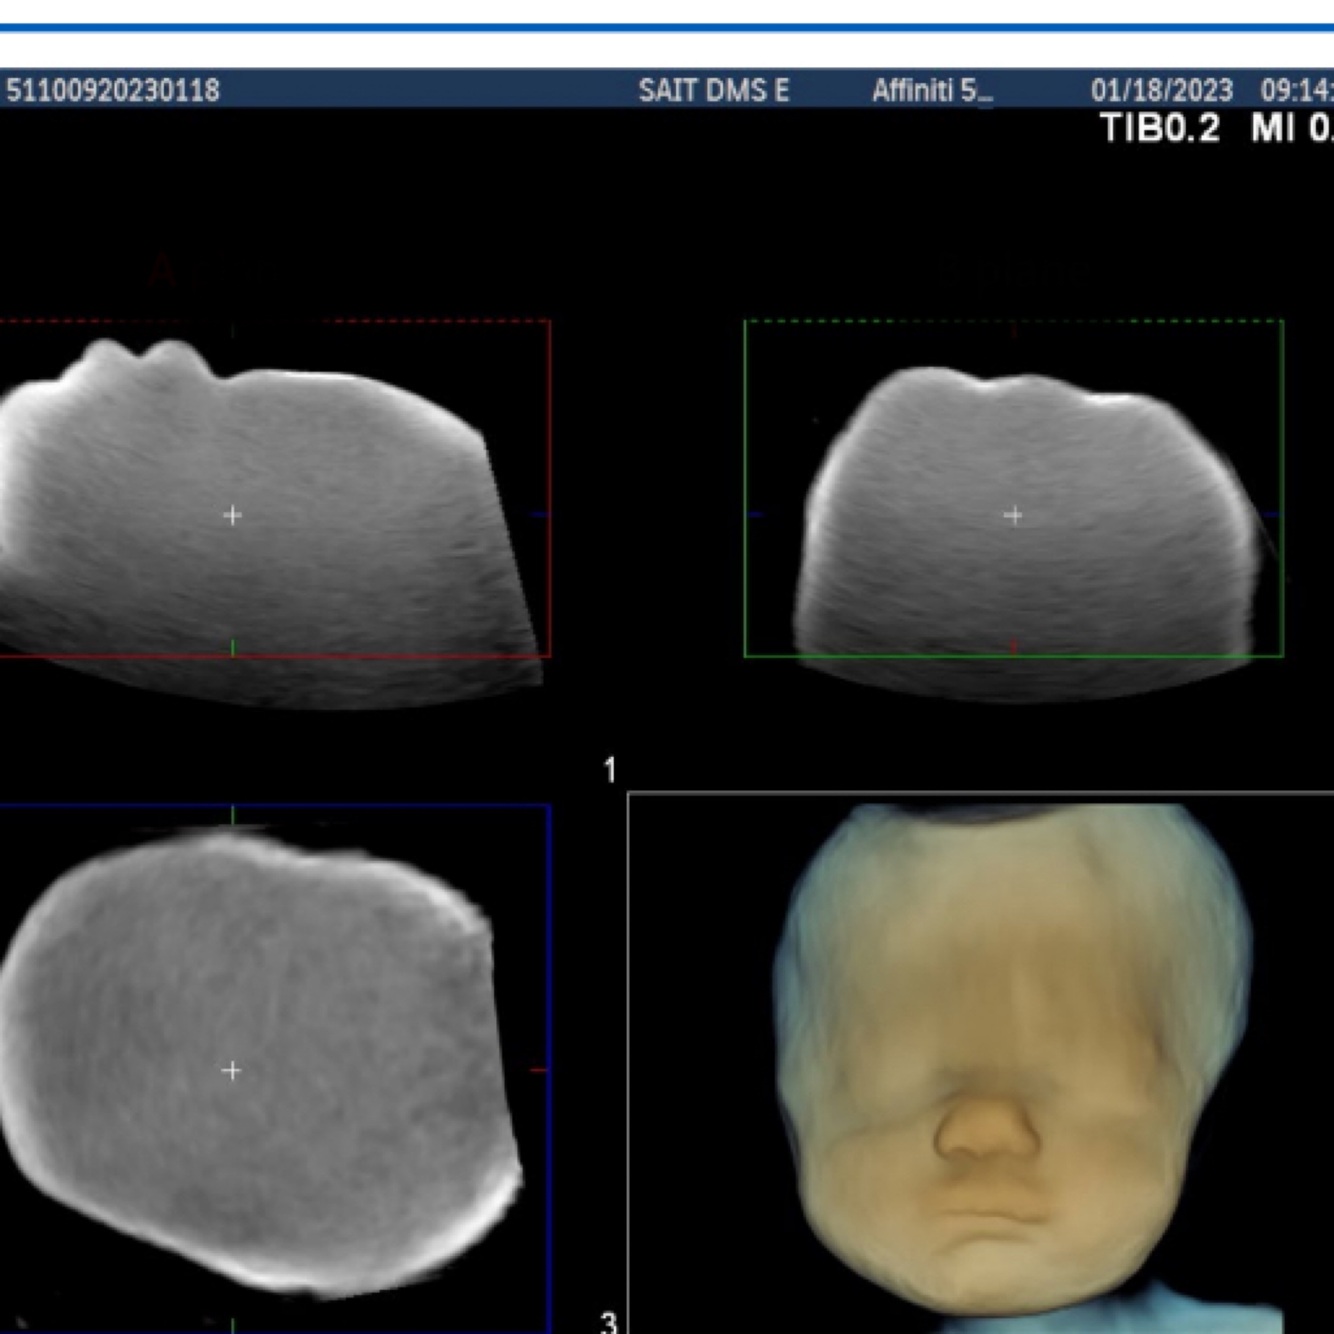

What is multiplanar reconstitution (MPR)?

This display type shows three plans (tomograms) of acquired data simultaneously

What are the three planes of MPR?

A, B, and C

What is the A plane?

Acquisition plane (Sag, Trans, Etc.)

What is the B plane?

90 degrees to the A plane vertically

What is the C plane?

Coronal plane

Which plane has the highest resolution? Followed by what?

1. A plane has the highest resolution

2. B then C planes respectively

Label the planes

What is the most. Recognized type of rendering mode in sonography, popular for 3D/ 4D images of the fetus?

Surface rendering

Surface rending mode shows what?

The superficial echoes, ignoring the underling anatomy

In terms of surface rendering, algorithms for shading and contour can do what?

Be applied to give the perception of depth